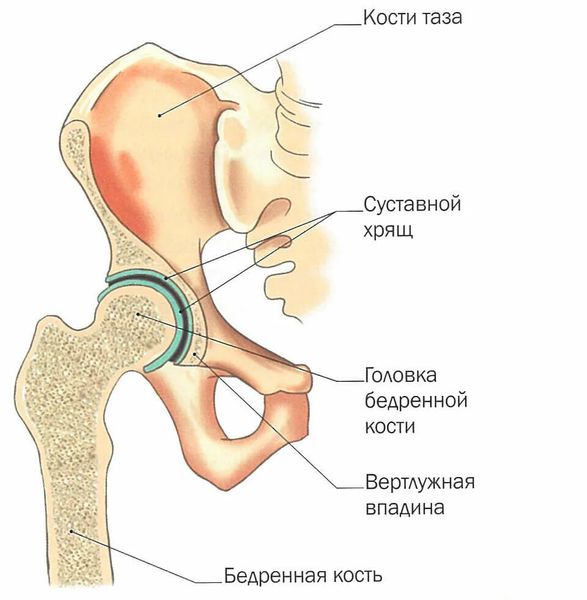

Механическая прочность тазобедренного сустава обусловлена его строением:

- Головка бедренной кости заходит в вертлужную впадину достаточно глубоко, что не даёт кости так просто «выскочить» из сустава.

- Вертлужная губа, прикреплённая к свободному краю вертлужной впадины, увеличивает её глубину и площадь контакта с головкой бедра, увеличивает плотность их прилегания и улучшает смазку сустава синовиальной жидкостью.

Строение тазобедренного сустава

- Связка головки бедренной кости, которая отходит от ямки вертлужной впадины, снаружи покрыта синовиальной оболочкой, а внутри содержит кровеносные сосуды. Они поставляют головке бедренной кости все необходимые вещества и не дают ей разрушаться.

- Сустав окружает капсула, которая состоит из мощных и прочных связок. Они образуют сплетение, которое плотно удерживает суставные поверхности, в том числе бедренную кость.